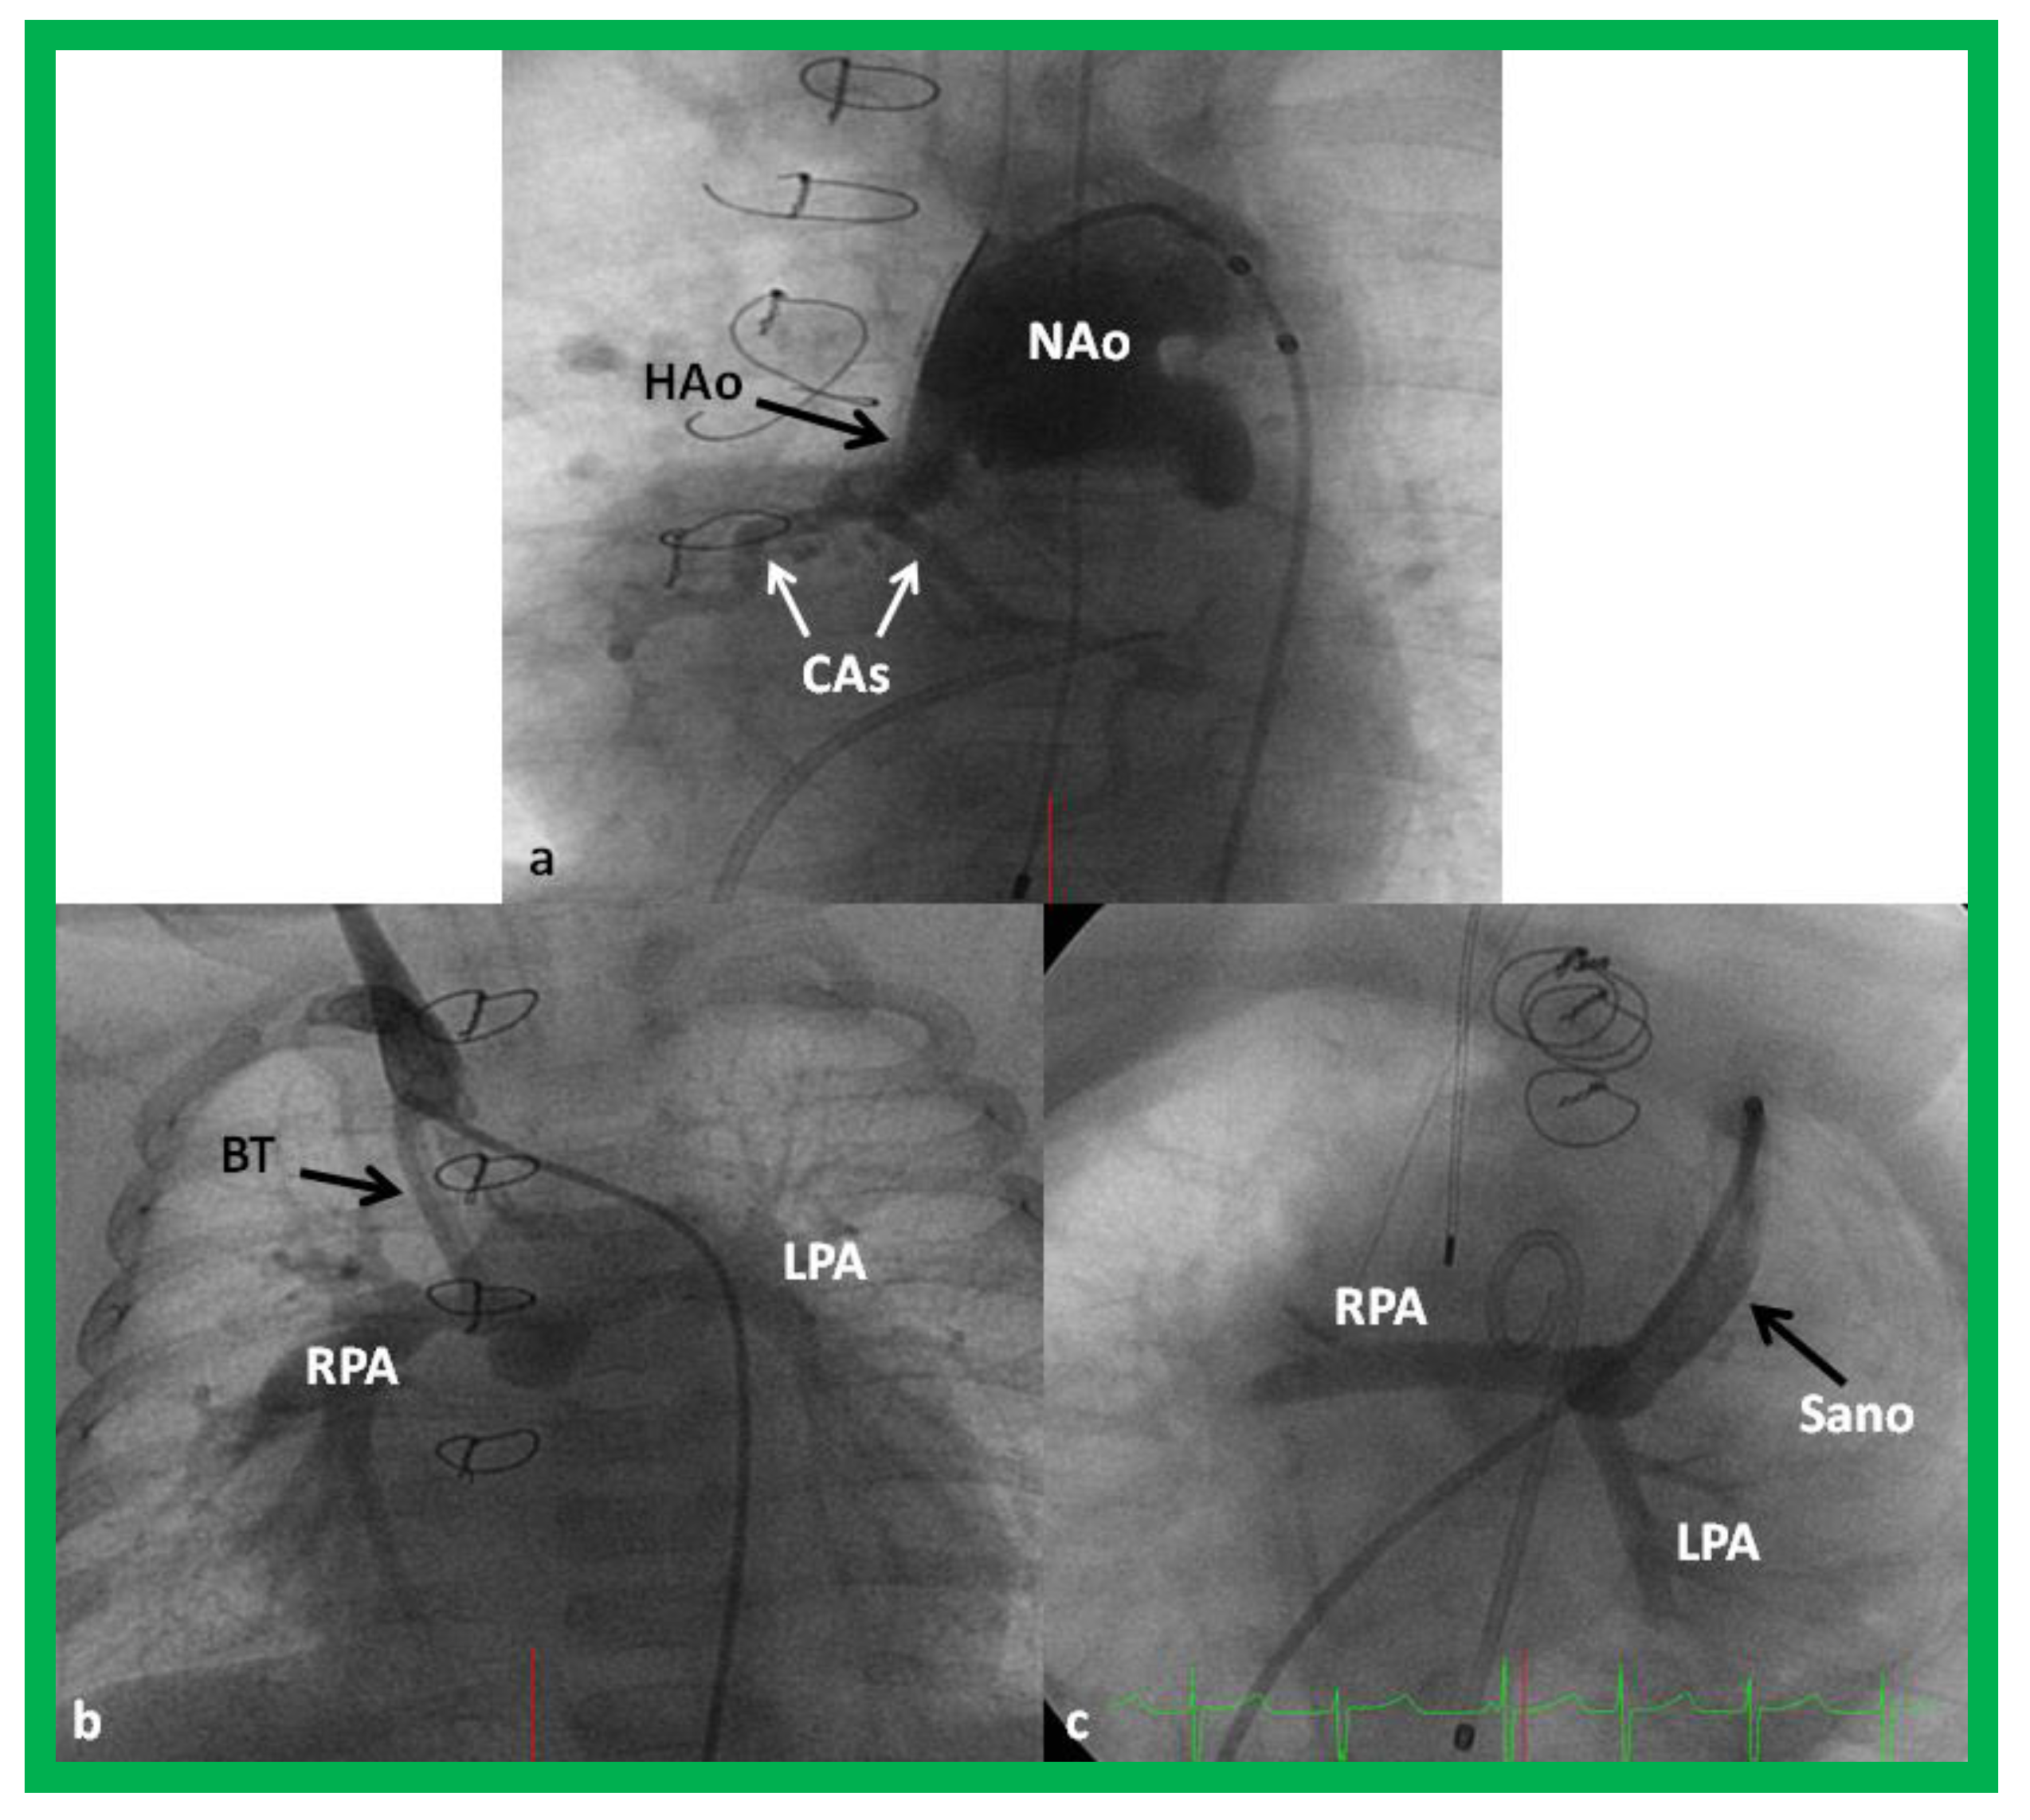

- Sano, S.; Ishino, K.; Kawada, M.; Arai, S.; Kasahara, S.; Asai, T.; Masuda, Z.; Takeuchi, M.; Ohtsuki, S. Right ventricle-pulmonary artery shunt in first-stage palliation of hypoplastic left heart syndrome. J. Thorac. Cardiovasc. Surg. 2003, 126, 504–509. [Google Scholar] [CrossRef]

- Sano, S.; Ishino, K.; Kado, H.; Shiokawa, Y.; Sakamoto, K.; Yokota, M.; Kawada, M. Outcome of right ventricle-to-pulmonary artery shunt in first-stage palliation of hypoplastic left heart syndrome: A multi-institutional study. Ann. Thorac. Surg. 2004, 78, 1951–1957, discussion 1957–1958. [Google Scholar] [CrossRef] [PubMed]